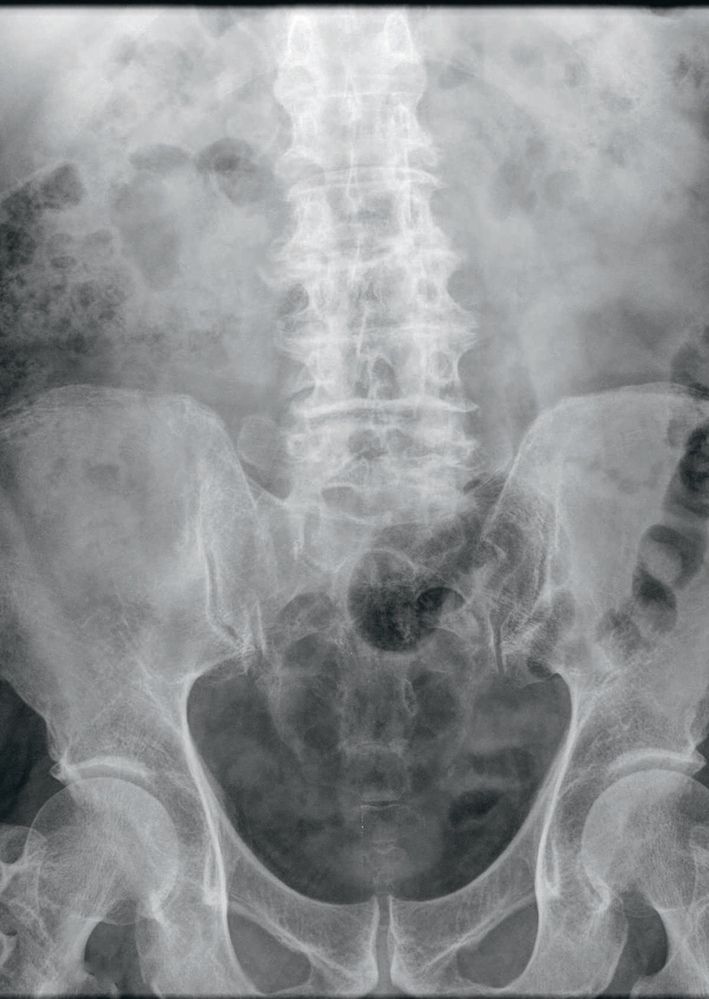

L’abdomen sans préparation

Constipation, douleur abdominale, colique néphrétique, ou encore recherche de corps étrangers… Les indications de la radiographie de l’abdomen sans préparation demeurent encore nombreuses, notamment dans le cadre de l’urgence.

À l’ère du scanner, du Pet-Scan, de l’IRM et autres examens d’imagerie sophistiquée, les bonnes vieilles méthodes ont un glorieux passé et encore un bel avenir, ne serait-ce que dans le débrouillage des pathologies abdominales communes qui ne relèvent pas, en première intention, d’examens d’imagerie complexe. C’est le cas de l’abdomen sans préparation, un examen rapide à exécuter (quelques minutes suffisent), qui peut être pratiqué dans n’importe quel service d’urgences et ne nécessite pas de préparation particulière, comme son nom l’indique (pas d’injection médicamenteuse ou d’ingestion d’un produit de contraste).